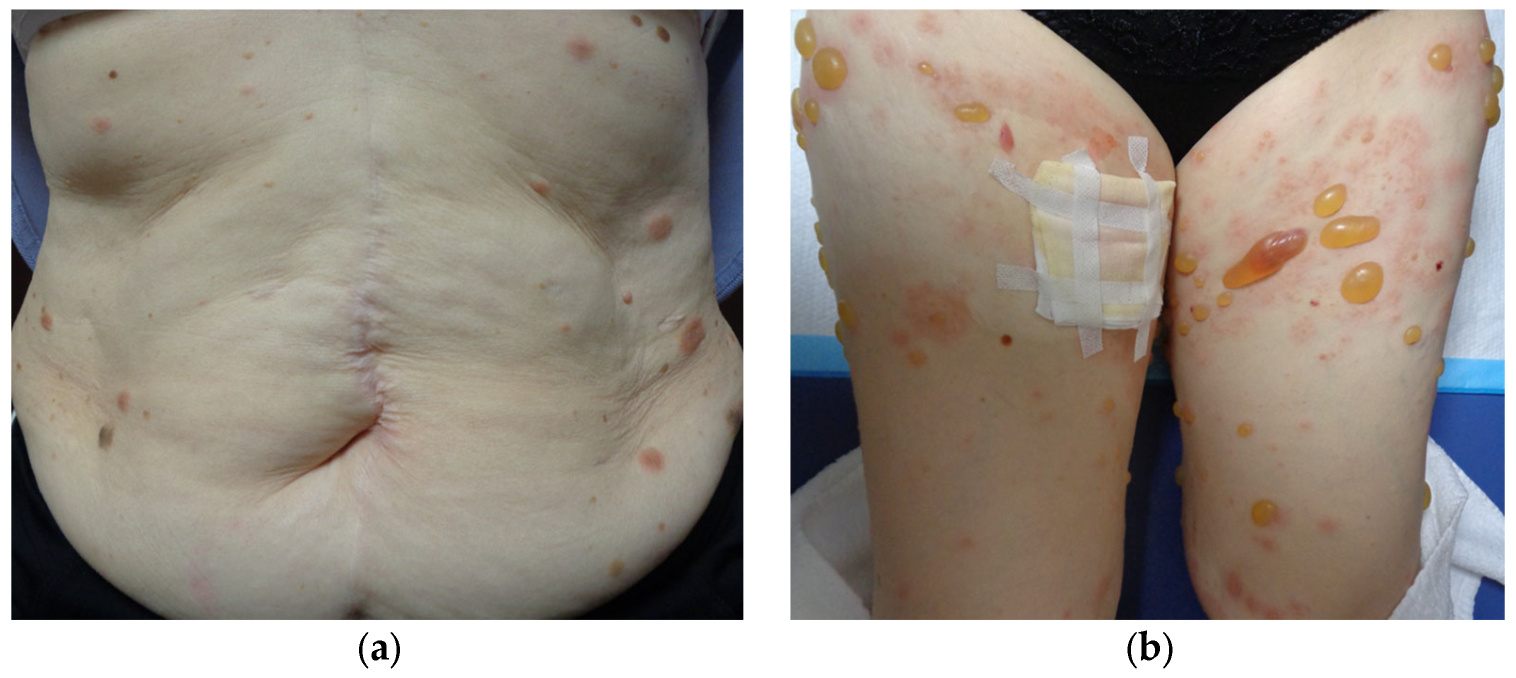

2. Case Presentation